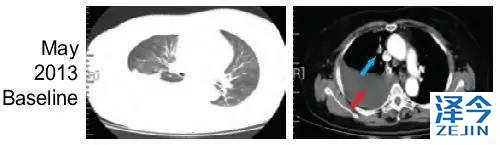

患者,女,62岁,无吸烟史,2013年5月因胸腔积液入院检查并治疗,被确诊为Ⅳ期肺腺癌。

化疗,一代TKI治疗后,病情依旧进展

患者先进行化疗,基因检测显示为EGFR 19号外显子缺失,开始使用一代TKI药物治疗。一代TKI耐药后,发现患者出现T790M突变。